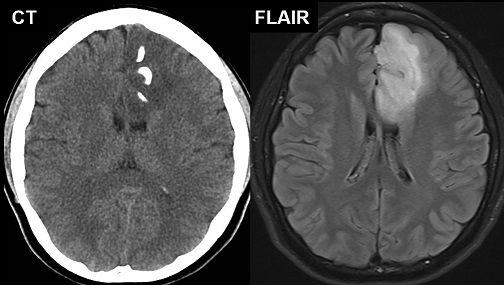

【112-1 醫學(四) 第74題】28歲女性,最近偶爾會有突發性的暈厥,腦部CT及MRI影像如附圖所示,下列敘述何者最不恰當?

詳解

破題關鍵

本題的關鍵在於辨識影像中病灶的鈣化(calcification)特徵,以及其在腦實質內(intra-axial)的浸潤性(infiltrative)生長模式,來判斷哪種腫瘤的可能性最低。

選項拆解

-A:此腫瘤有鈣化現象。正確。CT影像顯示病灶內有明顯的高密度鈣化點。